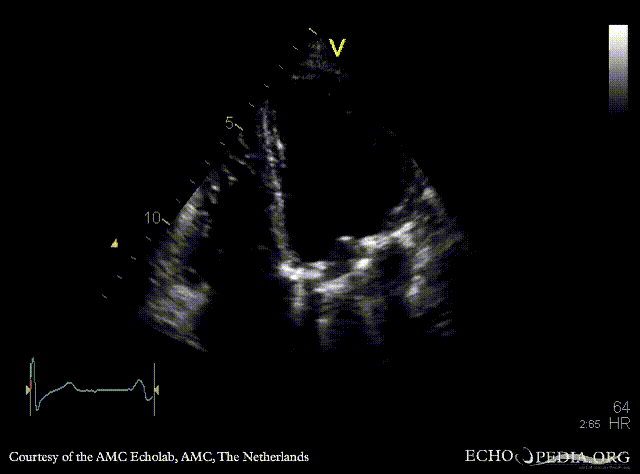

Mechanical mitral valve prosthesis

Courtesy of: AMC Echolab, AMC, The Netherlands

PLAX: mechanical mitral valve prosthesis, dilated left ventricle and left atrium PLAX with Color Dopler: no mitral regurgitation